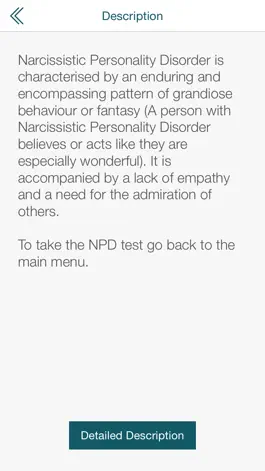

PocketShrink Narcissistic Personality Disorder allows a user who has concerns around having this personality disorder to get a rough gauge on whether they should seek proper medical advice. It also allows them to see which other (anonymous) users of the app have the same concerns as themselves.

Narcissistic Personality Disorder describes people who are grandiose, willing to step on others to get ahead and also easily injured. Although this may sound like your boss (partner, friends, teacher etc), using this app will allow you to get a more objective and accurate appraisal of their, or your own behavior.